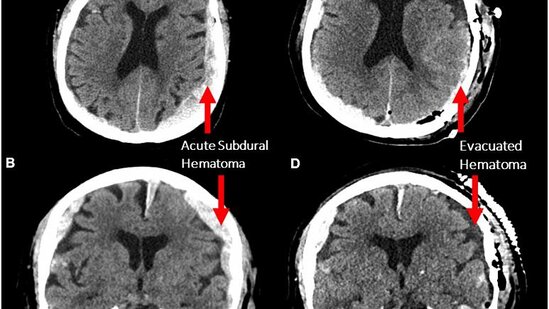

Epilepsiyadan müalicə alan 87 yaşlı xəstənin beyin fəaliyyəti elektroensefaloqrafiya (EEQ) ilə yoxlanarkən qəfil infarkt keçirib. Xəstə elektroensefaloqrafiyaya görə dünyasını dəyişərkən, onun son beyin fəaliyyəti 15 dəqiqə ərzində qeydə alınıb.

Alimlər müəyyən ediblər ki, ölən insanın beyni insan beyni ilə eyni "yuxular görən, keçmişi xatırlayan və ya meditasiya edən" fəaliyyətləri yerinə yetirir.

Araşdırmanın rəhbəri Dr. Ajmal Zemmar ölümdən əvvəl beynin insan həyatındakı mühüm anları sonuncu dəfə xatırlaya biləcəyini bildirib.